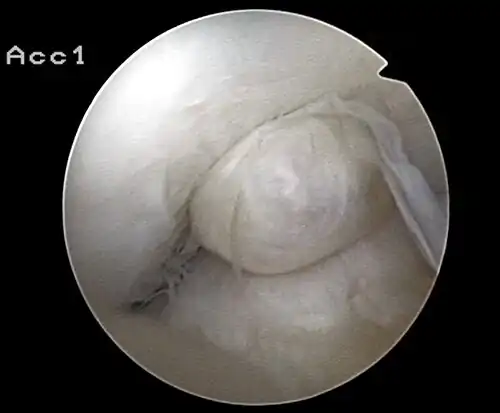

Arthroscopie diagnostique

La sécurité diagnostique la meilleure est obtenue par arthroscopie diagnostique. Ce procédé représente l'étalon-or pour le diagnostic de la rupture de LC. Ce procédé relève d'une chirurgie invasive au minimum, mais comporte certains risques, comme toute intervention chirurgicale dans le genou du patient[118]. Comme cependant le traitement chirurgical d'une rupture de LC sera conduit par chirurgie arthroscopique, il est possible d'enchaîner celle-ci immédiatement après l'arthroscopie diagnostique, par la résection partielle du ligament (pour une déchirure) ou la reconstruction en cas d'arrachement. Avec l'accroissement de la facilité de l'IRM, le nombre d'arthroscopies purement diagnostiques a nettement diminué ces dernières années[119],[120]. L'arthroscopie diagnostique est quand même utilisée comme précédemment comme procédé de choix pour une compréhension certaine du diagnostic de rupture de LC, en cas d'examen clinique confus et d'IRM difficile à interpréter[118].

Arthroscopie

L'opération proprement dite commence par l'introduction de l'arthroscope dans le genou du patient. Ceci permet de confirmer définitivement le diagnostic de rupture de LC. Les autres blessures, en particulier celles des ménisques, peuvent être soignées avant la reconstruction du LC.